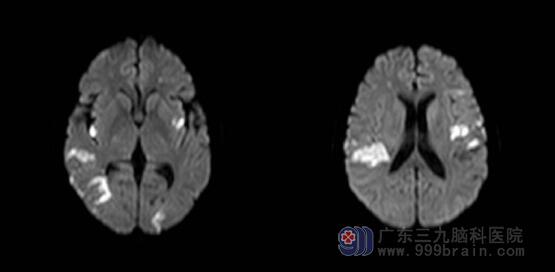

▲DWI:双侧小脑半球、双侧大脑半球、桥脑右侧多发脑梗塞(亚急性期),左侧额叶异常信号影。